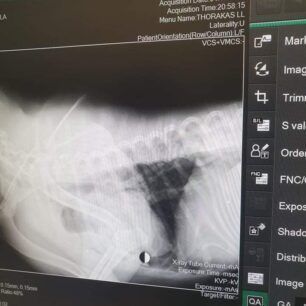

Το ζώο χειρουργήθηκε στις 9 Νοεμβρίου καθώς μεταξύ άλλων είχε και πυομήτρα. Οι ακτινογραφίες, που έβγαλε στην κλινική έδειξαν και τα πολλά σκάγια στο κορμί του – δηλαδή έχει πυροβοληθεί από κυνηγό – καθώς και το κάταγμα κνήμης και περόνης στο πόδι, το οποίο αντιμετωπίστηκε με νάρθηκα, αλλά και ο υγρό στον πνεύμονα (το όποιο αφαιρέθηκε με παρακέντηση). Είχε επίσης και εσωτερική αιμορραγία στην κοιλιακή χώρα.